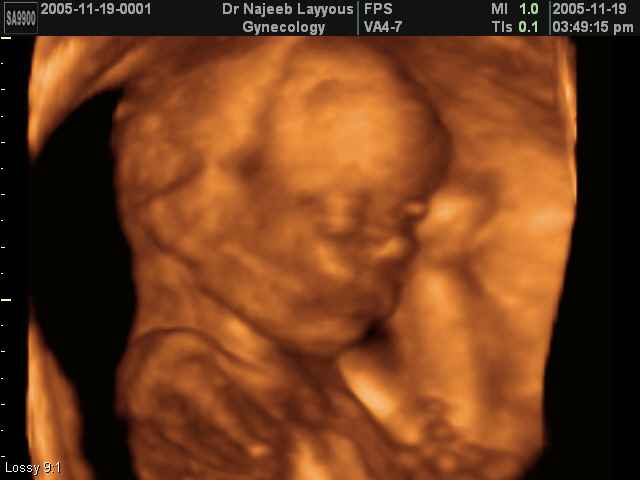

- 3D Fetal Profile Ultrasound Scan Photos

3D Fetal Profile Ultrasound Scan Photos | Dr N Layyous